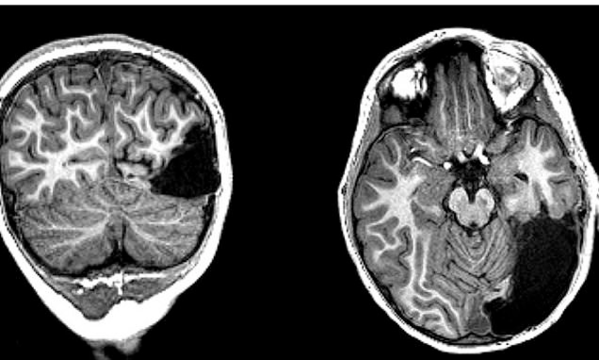

| Một phần não bị mất của Tanner. Ảnh: MSN |

Đáng ngạc nhiên, sau khi ca phẫu thuật cắt bỏ não được thực hiện, dù bị mất 15% bộ não, cậu bé vẫn nhận diện được khuôn mặt và vật thể ở bên mình. Theo các bác sĩ, có thể phần não bên trái của Tanner đã đảm nhận nhiệm vụ của phần bên phải bị mất.

Sau phẫu thuật, các bác sĩ theo dõi chặt chẽ cậu bé với sự hỗ trợ của máy cộng hưởng từ chức năng fMRI. Trong vòng 3 năm, Tanner được cho làm các bài kiểm tra thị giác và hành vi, để so sánh với những đứa trẻ khỏe mạnh khác ở cùng độ tuổi. Cậu bé có chỉ số IQ trung bình, kỹ năng nhận thức ngôn ngữ và thị giác phù hợp với lứa tuổi.